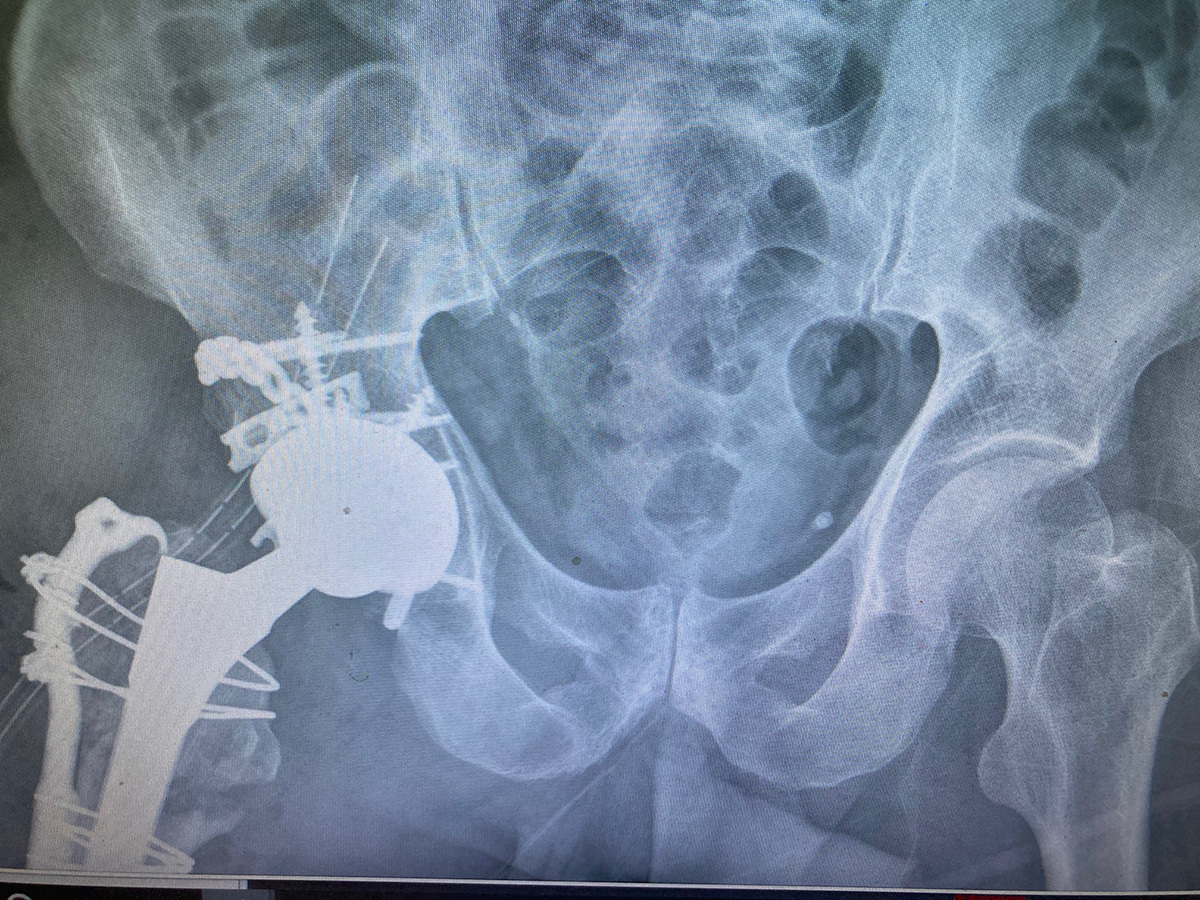

Το πρώτο βήμα κατά τη λήψη της απόφασης για την αντικατάσταση ισχίου είναι να συναντήσετε τον χειρουργό σας για να δείτε εάν είστε υποψήφιος για χειρουργική επέμβαση ολικής αρθροπλαστικής ισχίου. Ο χειρουργός σας θα πάρει το ιατρικό ιστορικό σας, θα κάνει μια φυσική εξέταση και θα ζητήσει ακτινογραφία του ισχίου σας. Ακόμα κι αν ο πόνος είναι έντονος και οι ακτινογραφίες δείχνουν προχωρημένη αρθρίτιδα της άρθρωσης, η πρώτη γραμμή θεραπείας είναι σχεδόν πάντα μη χειρουργική. Αυτό περιλαμβάνει απώλεια βάρους εάν χρειάζεται, πρόγραμμα άσκησης, αντιφλεγμονώδη φάρμακα, ενέσεις ή νάρθηκες. Εάν τα συμπτώματα συνεχιστούν παρά αυτές τις θεραπείες και με επιβεβαιωτικές ακτινογραφίες, τότε μπορείτε να εξετάσετε το ενδεχόμενο χειρουργικής επέμβασης.

Τα περισσότερα εμφυτεύματα σήμερα έχουν παρόμοια σχέδια και σχήματα, αλλά ο γιατρός σας θα καθορίσει ποια σχέδια λειτουργούν καλύτερα για το σώμα σας. Αυτά τα εμφυτεύματα είναι κατασκευασμένα από κοβάλτιο χρώμιο ή τιτάνιο. Μια μεταβλητή που παραμένει ακόμα είναι η επιφάνεια φόρτισης. Η επιφάνεια φόρτισης είναι η σφαίρα, η κεφαλή και η επένδυση που προσκολλώνται στο μηριαίο στέλεχος, και το κυπέλιο, η το κοτυλιαίο εμφύτευμα που στερεώνεται στο οστό. Η κεφαλή μπορεί να αποτελείται είτε από μέταλλο (κράμα χρωμίου κοβαλτίου) είτε από κεραμικό και η επένδυση μπορεί να είναι από πλαστικό (πολυαιθυλένιο), μέταλλο ή κεραμικό. Η κεφαλή και η επένδυση μπορούν στη συνέχεια να χρησιμοποιηθούν σε διαφορετικούς συνδυασμούς και ονομάζονται για τον αντίστοιχο συνδυασμό επένδυσης κεφαλή (μέταλλο σε πολυ, κεραμικό σε πολυ, κεραμικό σε κεραμικό κ.λπ.).

Το 2023, τα περισσότερα χρησιμοποιούσαν επένδυση πολυαιθυλενίου με κεραμική κεφαλή, ενώ άλλοι συνδυασμοί χρησιμοποιούνται με μικρότερη συχνότητα. Μπορείτε να συζητήσετε αυτές τις διαφορές με τον χειρουργό σας για να προσδιορίσετε ποιο εμφύτευμα είναι καλύτερο για εσάς.